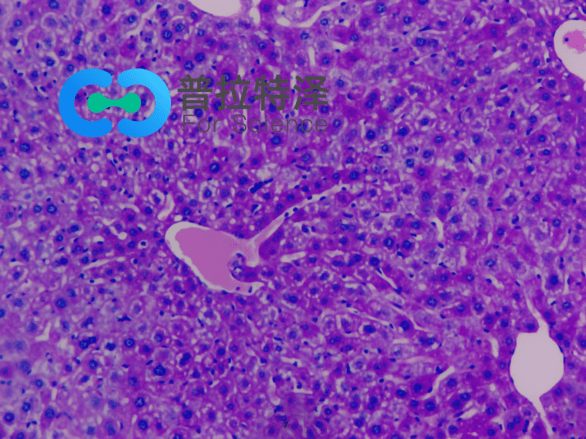

PAS染色實驗過程中常見問題解答由普拉特澤生物為大家總結分享。PAS染色作為一種在組織學中廣泛應用的染色技術,雖然具有高度的特異性和敏感性,但在實際操作過程中,也常會遇到一些問題和挑戰(zhàn)。本文是關于PAS染色實驗的最后一篇介紹,前面我們學習了PAS染色實驗材料有哪些?、PAS染色和mpo染色區(qū)別是什么?、PAS染色實驗注意事項以及PAS染色臨床應用,可以點擊標題直接傳送回去學習的哦。普拉特澤生物組織染色檢測平臺承接酵母雙雜實驗外包上百例,早就為大家把實驗過程中要踩的雷、吃的虧幫大家吃完了,現在我們就來看看,PAS染色中常見問題的解答:

綜上所述,PAS染色雖然是一種常用的組織學染色方法,但在實際操作中常常會遇到一些問題。通過掌握常見問題及其解決方法,我們可以更好地應用這項技術,提高染色效果和觀察結果的準確性。同時,不斷學習和實踐也是提高PAS染色技術水平的重要途徑。